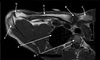

125

What is letter A?

MEDIAL FEMORAL CONDYLE

126

What is letter B?

MEDIAL COLLATERAL LIGAMENT

127

What is letter C?

MEDIAL MENISCUS

128

What is letter D?

TIBIAL PLATEAU

129

What is letter E?

LATERAL MENISCUS

130

What is letter F?

LATERAL COLLATERAL LIGAMENT

131

PATELLA

132

FEMUR

133

ANTERIOR HORN OF LATERAL MENISCUS

134

TIBIA

135

HEAD OF FIBULA

136

POSTERIOR HORN OF LATERAL MENISCUS

137

QUADRICEPS TENDON

138

139

PATELLA TENDON

140

141

POSTERIOR CRUCIATE LIGAMENT

142

DISTAL FEMUR